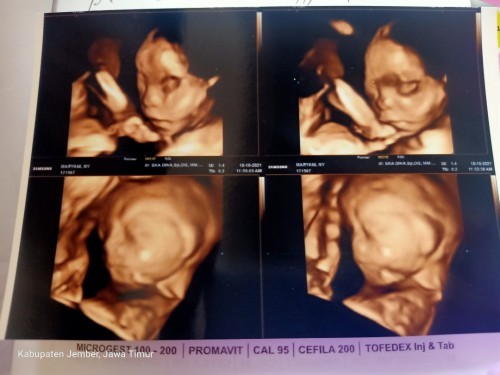

Baby twins

Alhamdulillah baby twins berjenis kelamin laki2 semua udah gak sabar pengen ketmu jagoan sehat trus smpek lahiran ya dan semoga mendekati lahiran posisi bagus Krn skrng posisi melintang semua dan harus cek up setiap bulan.... Sehat selalu jagoan bunda.... #firstbaby